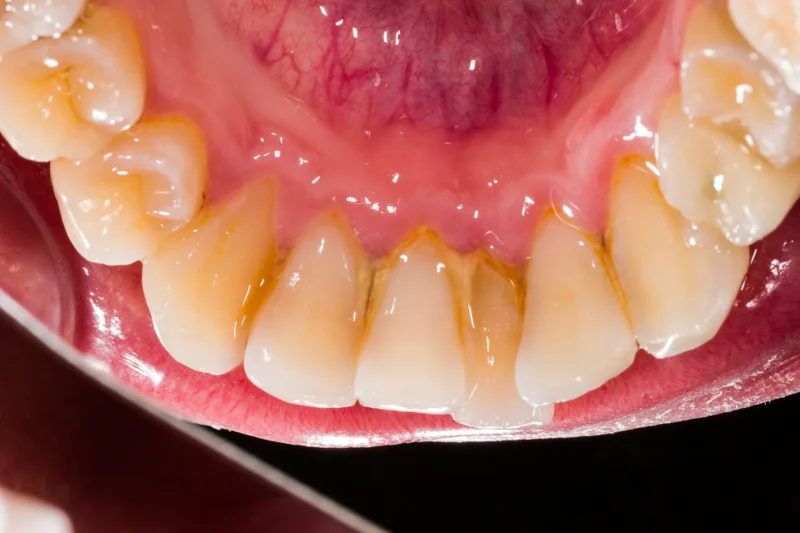

Tartar (also known as calculus) forms when plaque hardens due to minerals in your saliva. Once it hardens, it sticks firmly to your teeth and gumline.

Unlike plaque, tartar cannot be removed with regular brushing. It requires professional cleaning or specialized tools to break it down. This is where many people go wrong—they continue brushing harder, thinking it will solve the issue, but it doesn’t.

Tartar feels rough, hard, and crusty. - Color

Plaque is usually colorless or pale.

Tartar can appear yellow or brown. - Removal Method